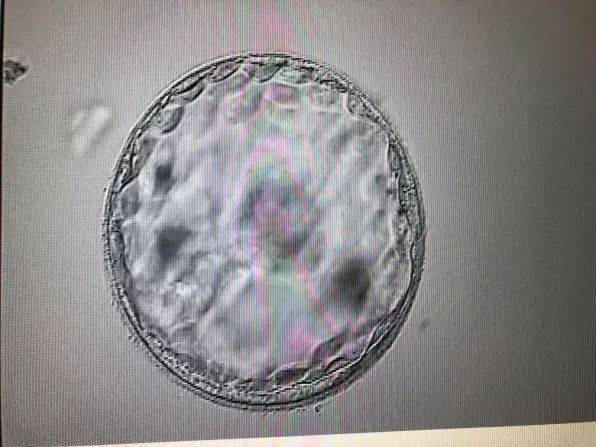

胚胎着床是妊娠过程中的一个关键阶段,通常发生在受精后6-10天。在这个过程中,受精卵从输卵管移动到子宫,并嵌入子宫内膜。这一过程对于妊娠的成功至关重要。许多女性在胚胎着床后,会出现一系列的生理和情绪变化,包括胚胎着床后感觉会消失吗的问题。